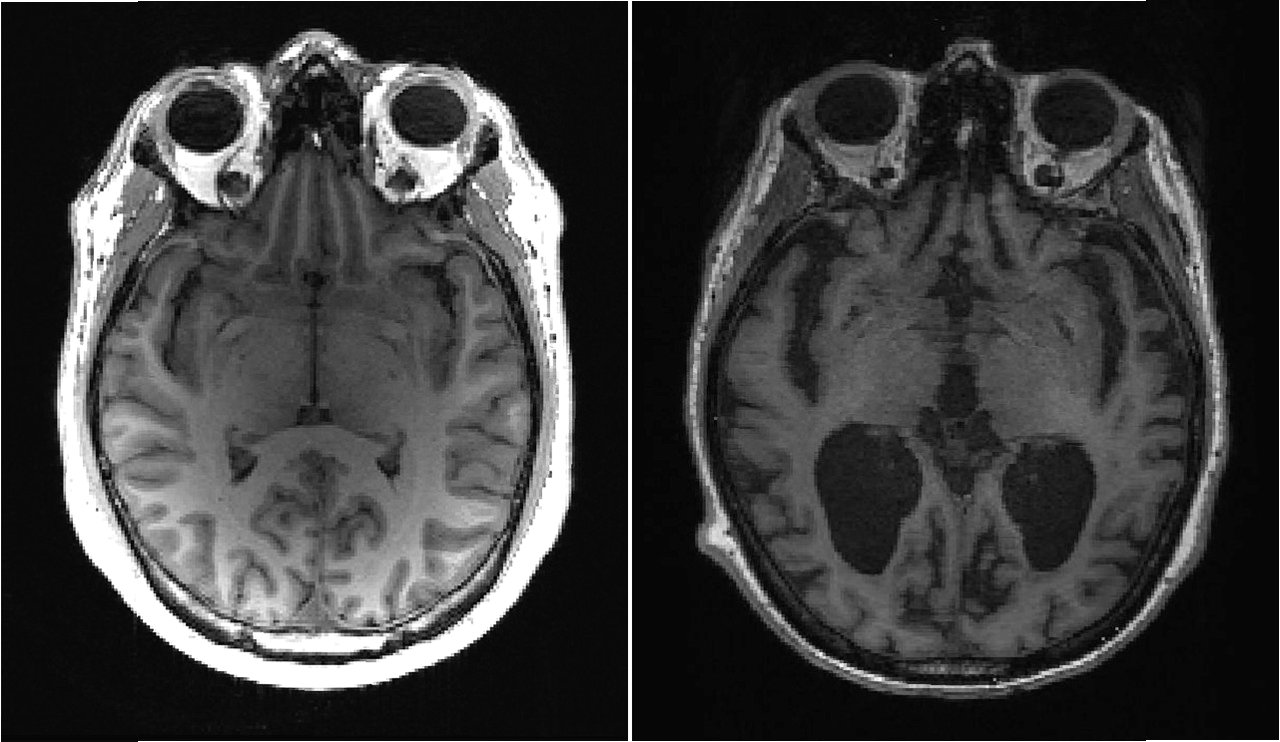

5. 뇌 영상 촬영: MRI, PET 등의 뇌 영상 촬영을 통해 뇌의 구조적 변화나 대사 활동을 확인합니다.

3. 뇌 영상 지표: 뇌 위축, 포도당 대사 감소 등 뇌의 구조적, 기능적 변화를 나타냅니다.